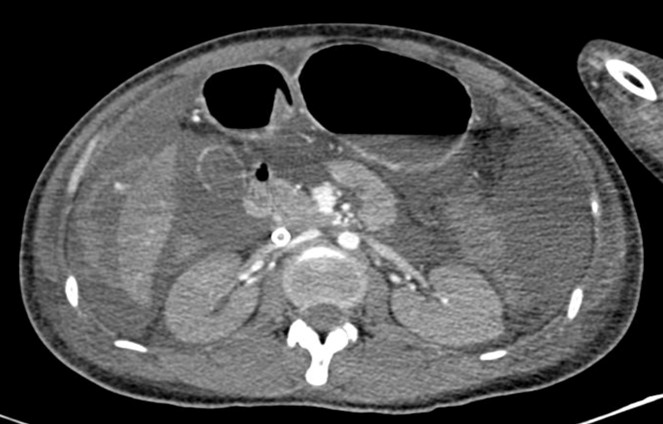

Những tưởng đã tạm ổn, bệnh nhân lại đối mặt nguy cơ mới: mất máu cấp, Hemoglobin chỉ còn 5,5 g/dL. Việc tìm nguyên nhân và bù máu khối lượng lớn càng khó khăn vì bệnh nhân có nhóm máu A Rh (-) – nhóm máu cực hiếm. Ngay lập tức, bệnh viện liên hệ Bệnh viện Truyền máu Huyết học, đồng thời huy động người hiến máu cùng nhóm, trong đó có nhân viên y tế sẵn sàng tiếp máu cho bệnh nhân. Song song đó, siêu âm và CT cho thấy dịch ổ bụng lượng nhiều, nghi máu trong ổ bụng. Êkip ngoại khoa nhanh chóng đưa bệnh nhân lên phòng mổ trong tình trạng ECMO vẫn đang hoạt động. Ổ chảy máu tại phân thùy VI của gan được đốt cầm máu thành công.